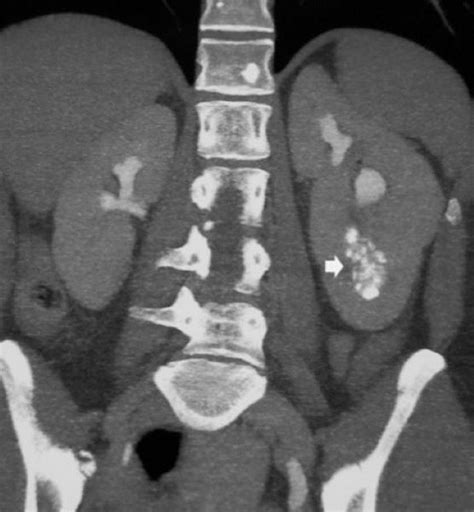

• Presence of kidney stones or calcifications.

In such cases, additional imaging techniques like CT scans or MRI may be recommended to complement the USG findings.

Case Study 2: A 45-year-old patient with a history of kidney stones underwent a Medullary Sponge Kidney USG, which showed enlarged kidneys with a spongy appearance and multiple calcifications. The patient was advised to follow a low-calcium diet and increase fluid intake, which helped in preventing further stone formation and maintaining kidney function.

• medullary sponge kidney ultrasound images

• medullary sponge kidney ultrasound appearance

• medullary sponge kidney vs nephrocalcinosis